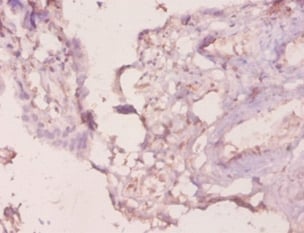

IHC (Immunohiostchemistry)

(Immunohistochemical analysis of paraffin-embedded human-colon using antibody diluted at 1:50.)